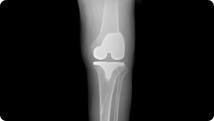

Radiographic image of knee arthritis Radiographic image of a total knee replacement

Knee Arthritis

Total Knee Replacement